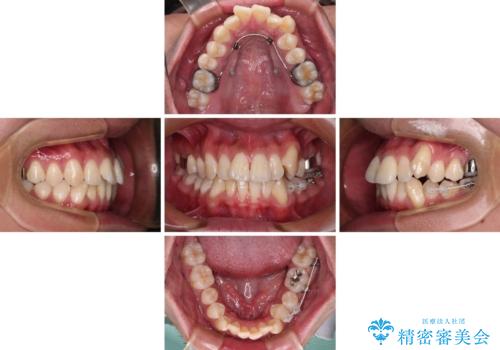

歯列としてはインビザラインでもワイヤー矯正でも対応できるものでしたが、上顎の八重歯や下顎小臼歯の捻転といったインビザラインでは時間のかかってしまう歯列不正が認められたため、補助装置やワイヤー矯正を治療当初に使用することで、インビザラインによる治療をスムーズに行えるように計画しました。

インビザラインは得意・不得意の差がはっきりとしているため、ワイヤー装置などをうまく活用することで、治療期間を短縮するとともに、より理想的な仕上がりを達成することができます。